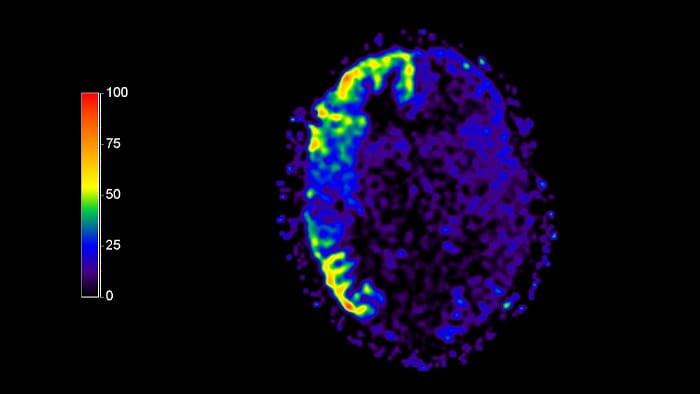

3D ASL